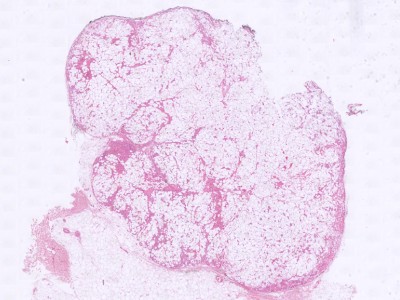

![Histologie angiolipoma (click on photo to enlarge) [source: Kevin Kwee / Afdeling Pathologie MUMC] Histologie angiolipoma](../../../pacoupes/thumbnails/angiolipoom-1.jpg) |

ingescande coupe (zoom) |